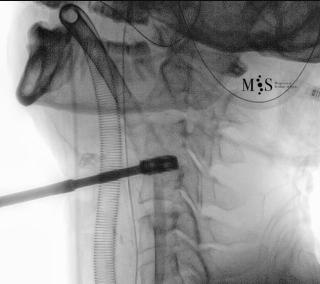

Images showing the endoscopic placement of a cage into a cervical disk

Animated image showing the endoscopic insertion of an intervertebral cage into a cervical disk.

Note the distraction of the disk space during as the cage is inserted.

Endoscopic ACDF starts with an endoscopic discectomy to decompress neural structures, like the spinal cord, and prepare the disk for the cage placement. Once the interbody cervical disk has been prepared, the an interbody device is percutaneously placed into the disk. This device can either be a titanium interbody cage to achieve vertebral fusion or a disk prothesis that allows to restore movement in the cervical spine. The placement of the device is done unter x-ray fluoroscopic control and direct endoscopic vision, see the animation on the figure at the right side of this page.